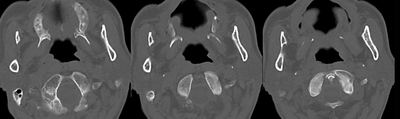

右侧咽隐窝变浅,相应软组织增厚。考虑:鼻咽癌复发。

右侧咽隐窝变浅,沿旁间隙存在,结合病史考虑鼻咽癌复发。

从影像学角度考虑,虽然两侧扫描时不对称,但是右侧还是存在病变,应该考虑鼻咽癌改变,与炎症鉴别----mr